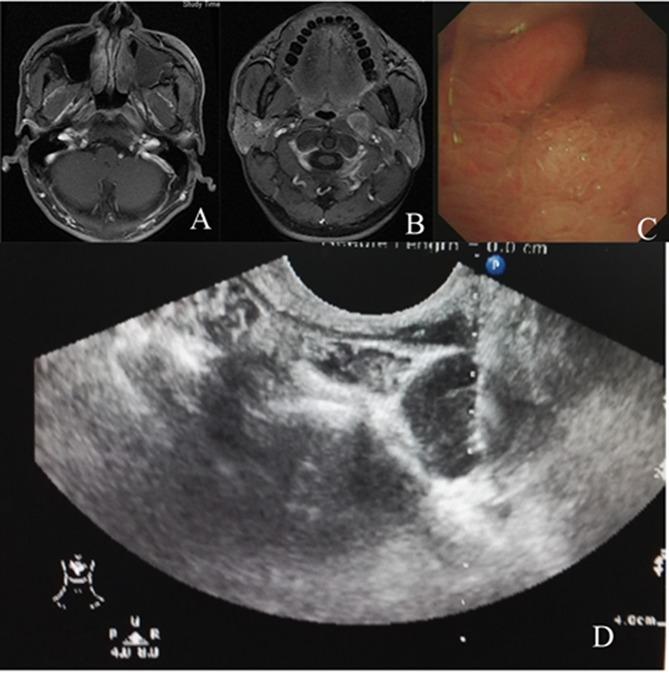

From January 2005 to January 2015, patients who presented with enlarged retropharyngeal nodes underwent transoral sonography-guided fine-needle aspiration to confirm histology. Those with metastatic undifferentiated SCC with unknown primary tumors were treated with radical radiotherapy to nasopharyngeal mucosa plus bilateral neck. Chemotherapy was administered for patients staged N2-3. Endpoints included metastatic nodes control, the appearance of primary tumor, overall survival and treatment-related toxicities.

2005年1月至2015年1月,对出现咽后淋巴结肿大的患者进行经口超声引导下细针穿刺以确诊组织学类型。对原发肿瘤不明的转移性未分化SCC患者,采用对鼻咽黏膜加双侧颈部进行根治性放疗。N2-3期患者给予化疗。观察终点包括转移性淋巴结控制情况、原发肿瘤的出现情况、总生存率和治疗相关毒性。